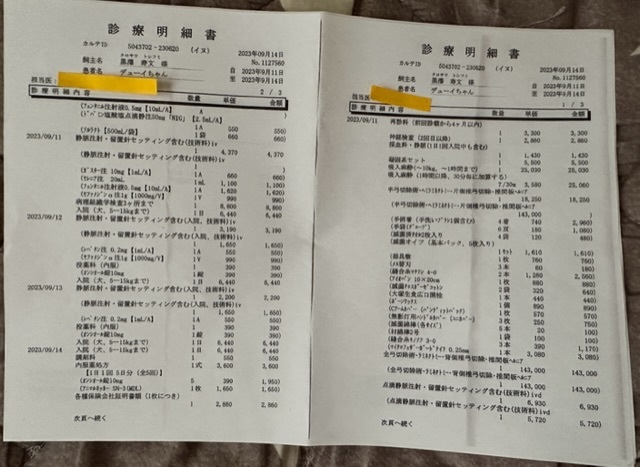

★手術は一日も早くとの事で

大学病院のご配慮もあり9月中旬に受けることが出来ました。

手術は予定通り行われました。

引っ張られていた膜瘤を切除

一部骨を削ったそうです。

手術的には想定通りの内容で成功

※上記は大学病院で頂いた診断書

※下記は初診かつ、会陰形成術をして頂く動物病院より発行して頂いた診断書、治療計画書

実際にかかった治療費

大学病院での手術、入院費